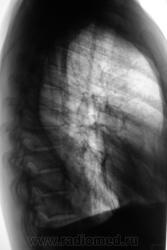

Очаговый ТБС л-х, ф инфильтрации. Осложнение - 2стор. экссудативный плеврит.

Паракостальный двусторонний плеврит,срава - от ключицы до купола(осумкованный),слева-от 5 до 8 ребра.Викарная эмфизема слева.

Сливная долевая пневмония в средней доле справа, очаги справа в верхней доле, экссудативный, частично осумкованный задний правосторонний плеврит. Обязателен анализ экссудата после пуннкции и контрольные снимки, чтобы не пропустить тбс, но он маловероятен - быстрая? динамика

Осумкованные плевриты, оч.твс левого л-го ст. кальцинации.

Осумкованный выпот в плевральных полостях с 2-х сторон, справа по задней пристеночной плевре.На прямой томограмме на 8см. очаговоподобные тени( туб. очаги?).Можно предположить, осумкованный плеврит спицефической этиологии.

Правосторонний паракостальный осумкованный плеврит, в Д-2 полиморфные очаги. Слева плевр. наслоения, небольшое паракост. осумкование, в верхушечном сегменте (1-2) очаги, лимфангит, уплотнение апикокост. плевры.

Да, у пациента диагностирован и подтверждён двусторонний очаговый туберкулёз и задний паракостальный осумкованный плеврит.